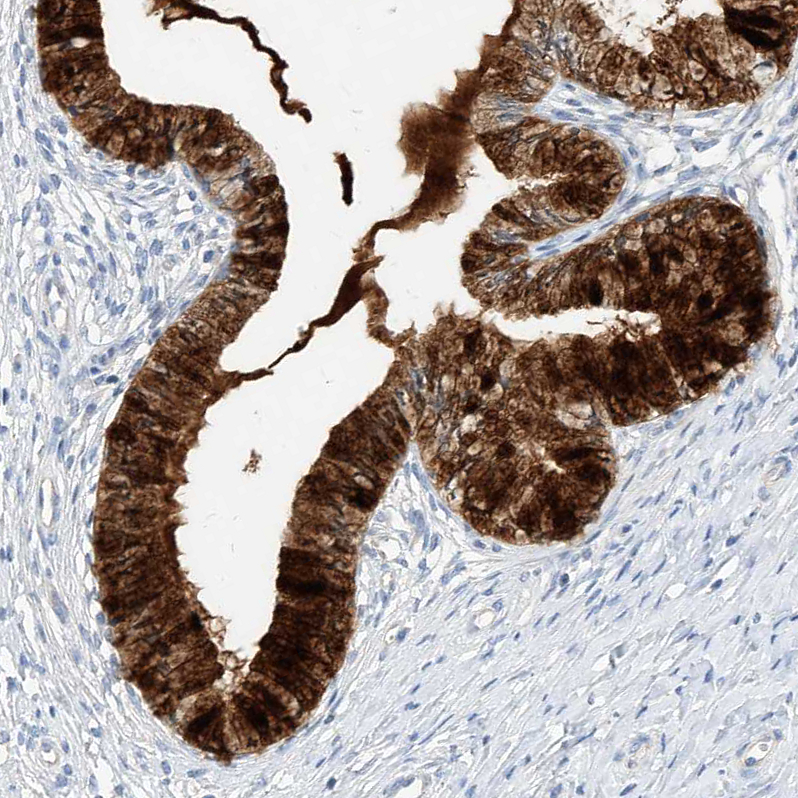

Immunohistochemistry analysis in human cervix, uterine and lymph node tissues using HPA034584 antibody. Corresponding SCGB2A1 RNA-seq data are presented for the same tissues.